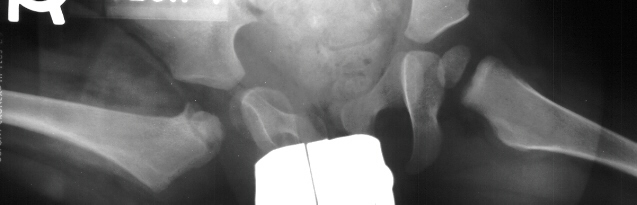

This case is an example of untreated septic arthritis which caused avascular

necrosis of the proximal femur. The primary cause of this is undrained

septic hip. Repeated aspiration is not adequect treatment of a septic hip.

- Post Operative Day 18: R hip Xray: subluxation of R hip, possible metaphyseal

lucency consistent with osteomyelitis. Taken to OR for repeat I & D

of R hip via posterior approach with Penrose drains and hip spica cast